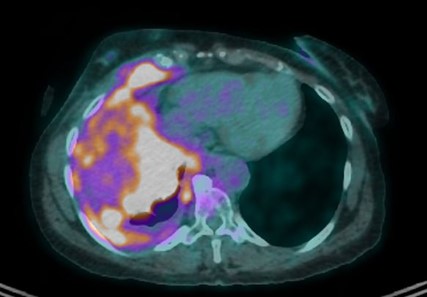

Twelve months since the end of chemotherapy the patient on a combined maintenance by bevacizumab and olaparib presents complete metabolic response with very good partial response on her imaging (Fig. 5) and her CA 125 in negative at 19kU/L. No dose adaptation was necessary, and no significant toxicities were reported. Fig. 6 shows the treatment ant evolution timeline.

Figure 5: Response to chemotherapy.